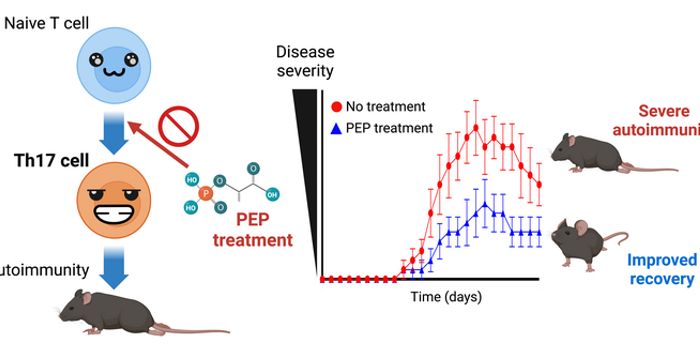

MAR 13, 2023Drug Discovery & DevelopmentA team of researchers from the Okinawa Institute of Science and Technology (OIST) have developed a new chemical compound ...